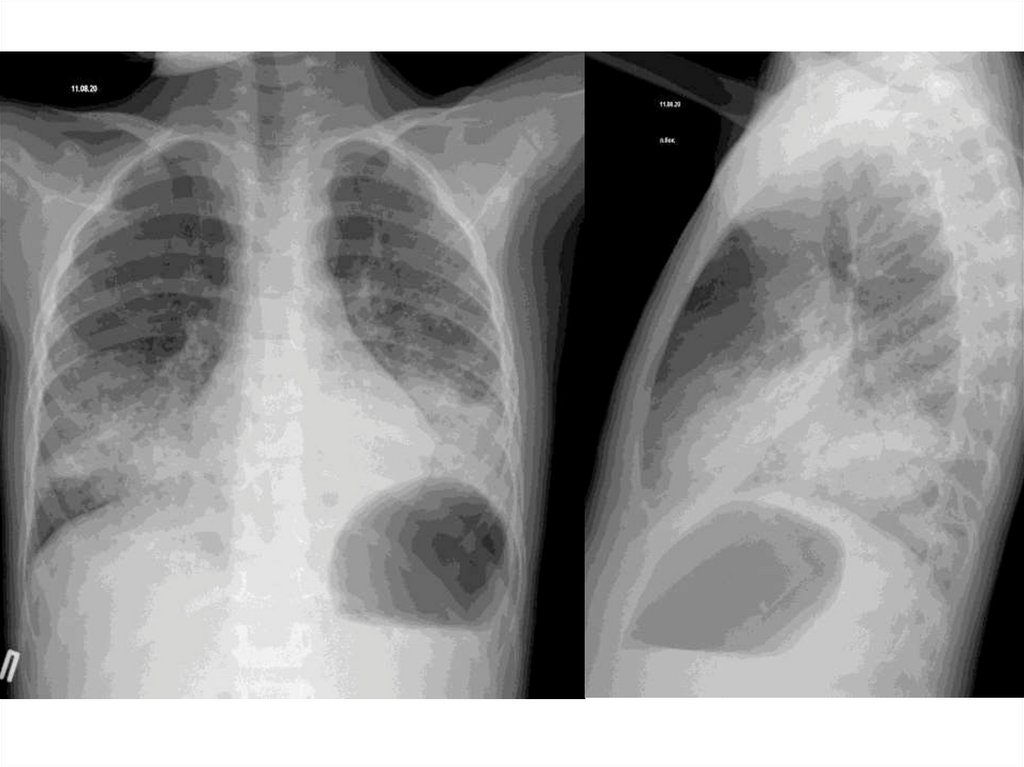

Пациент №1

5лет

Анамнез заболевания: 04.08.2020 около 17 часов ребенок, находясь в

автомобиле с дедушкой, выпил жидкость для розжига костра из бутылочки

для детской воды, не более 1 глотка со слов бабушки ребенка. В 17.45

самостоятельно обратились в БСМП №2, где был выполнен осмотр,

зондовое промывание желудка до чистых вод, характерного запаха для

растворителя не было выявлено. По согласованию с доктором ОДБ

ребенок в удовлетворительном состоянии направлялся в ОДБ для

динамического наблюдения и симптоматической терапии. Однако процесс

транспортировки ребёнка в ОДБ вмешался отец, забрал и увез ребенка

домой. 04.08.2020 около 21:00 часа у ребёнка возникло недомогания.

Вызванное СМП , доставлен, госпитализирован в Детскую больницу №1.

Диагноз: J15.9 Внебольничная двухсторонняя S5,6,7,8,9,10 справ и

S5,8,9,10 слева очагово сливная пневмония, тяжёлое, острое течение.

Острое пероральное отравление жидкостью для розжига костра

(бензинсодержащее, парафинсодержащее) тяжёлое течение.